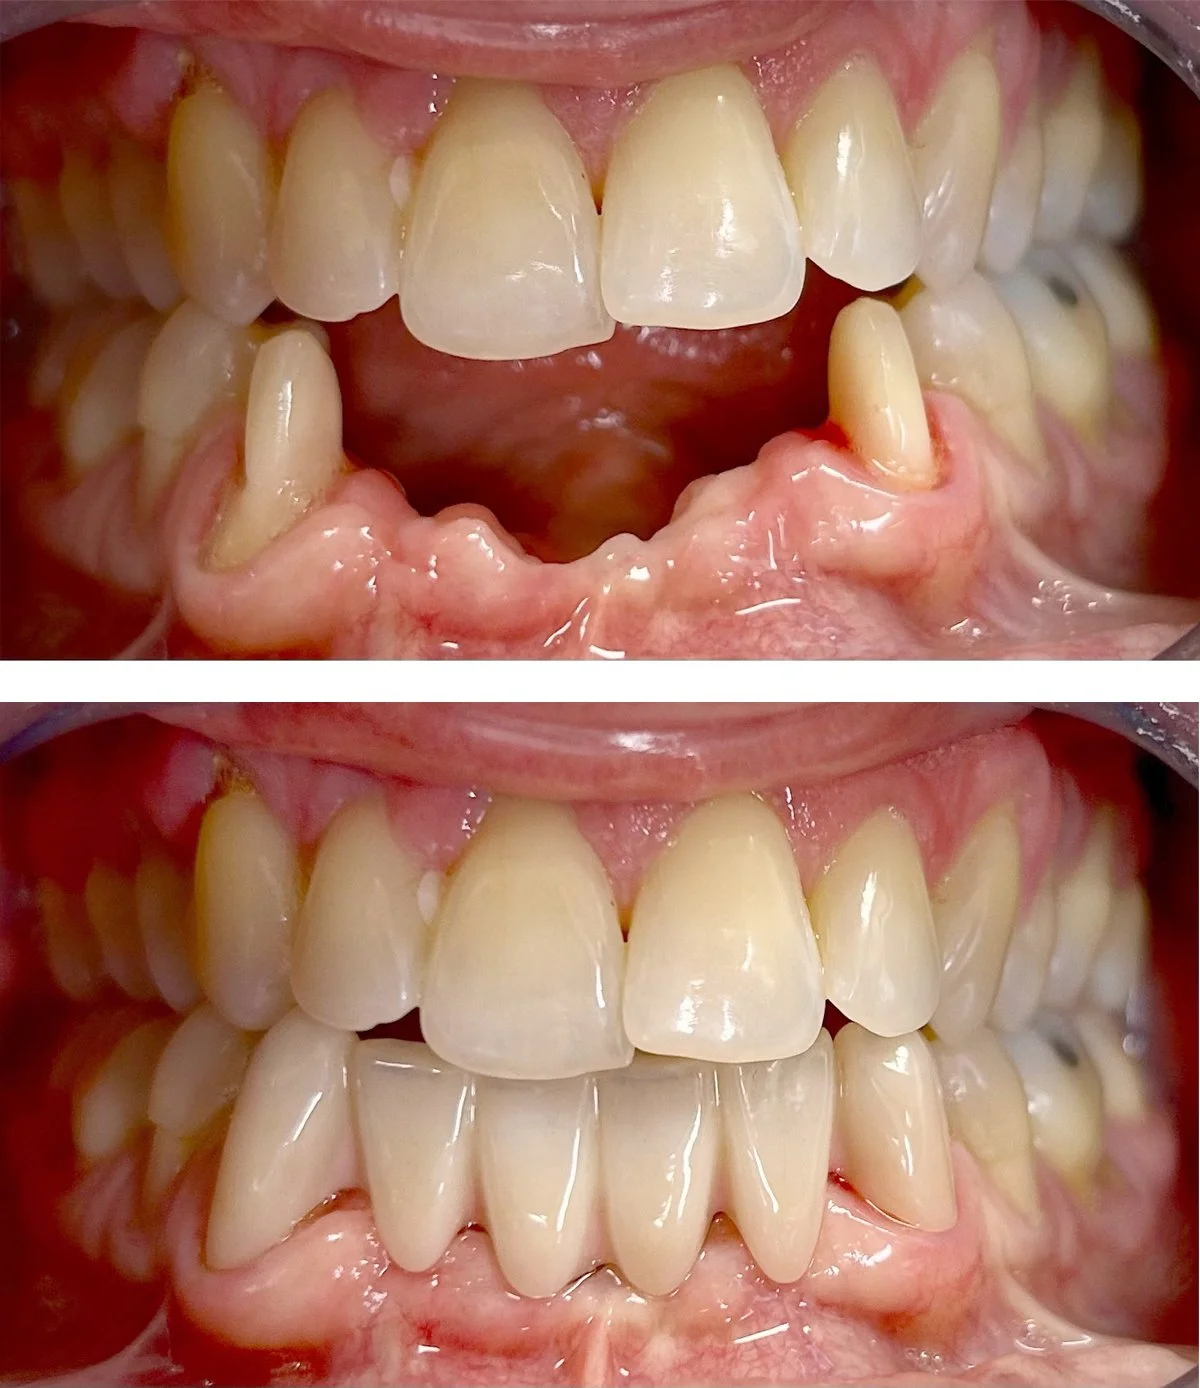

Emergencies

Relief from pain is the primary objective. Temporary and long term solutions available based on the clinical scenario.

Tooth Fracture